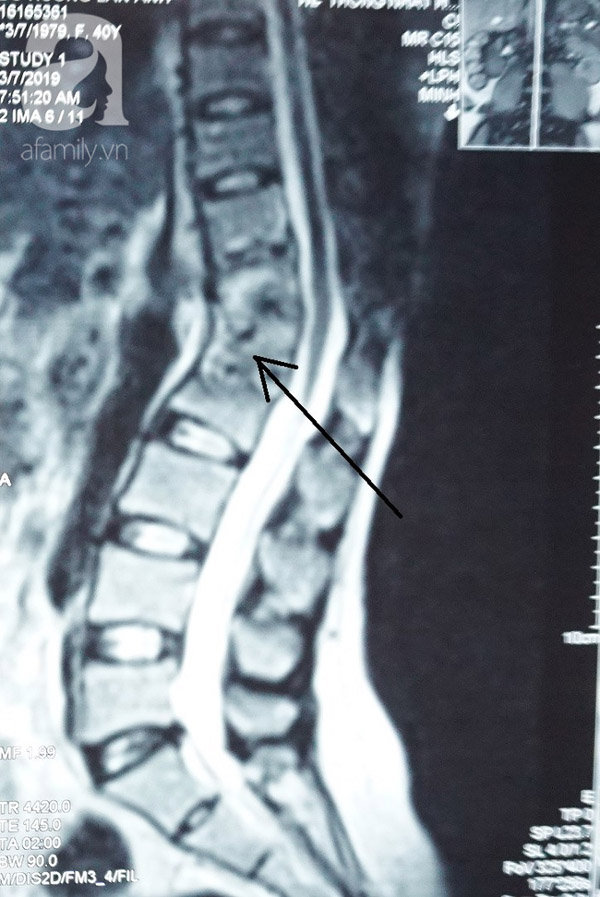

Kết quả chụp MRI tại Bệnh viện cho thấy bệnh nhân A. bị lao cột sống 4 đốt D11-D12, L1-L2, có khối áp xe to dọc cơ thắt lưng chậu trái. Trước tình hình trên, bệnh nhân được chỉ định phẫu thuật ngay để tránh biến chứng.

Lao cột sống 4 đốt D11 D12 – L1 L2.